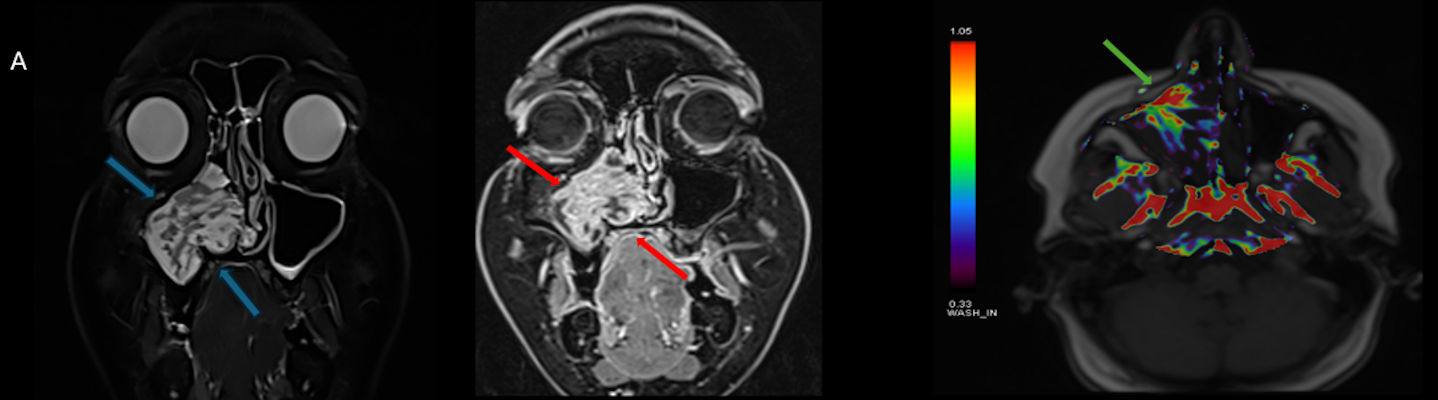

- A) Koronal T2 ağırlıklı görüntülerde sol maksiller sinüs lümenini dolduran, belirgin ‘convoluted’ (karmaşık-kıvrımlı) serebriform patern sergileyen lezyon (oklar), kontrastlı seride heterojen ve yoğun kontrastlanma göstermektedir (oklar). Perfüzyon incelemesinde pedinkülünde perfüzyon artışı gösterdiği, diğer kontrastlanan segmentlerin nispeten hipoperfüze olduğu görülmektedir (ok).

- MR incelemesinde sinonazal inverted papilloma tipik olarak T2 ve post-kontrast T1 serilerde ‘convoluted’ serebriform paternde heterojen sinyal ve kontrastlanma gösteren, pedinküler orijininde daha belirgin perfüzyon artışı sergileyen, genellikle difüzyon kısıtlaması izlenmeyen ve komşu sinüs duvarlarında ekspansiyona bağlı remodelinge yol açabilen benign ancak lokal agresif karakterde bir yumuşak doku kitlesi olarak izlenir.